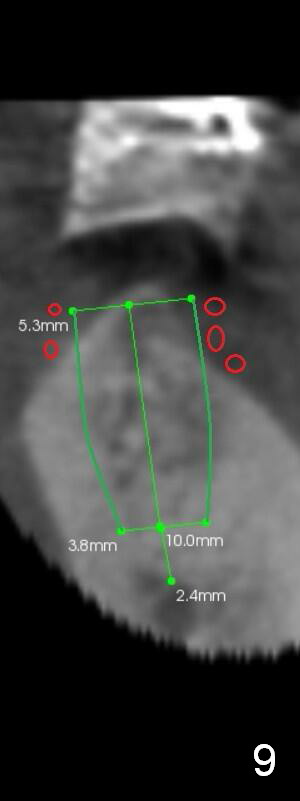

The implant at the site of #18 could be placed at the crestal level with bone graft (Fig.9: 5x10 mm). Or a shorter implant is placed deeper with or without grafting (Fig.10: 5.3x8 mm).